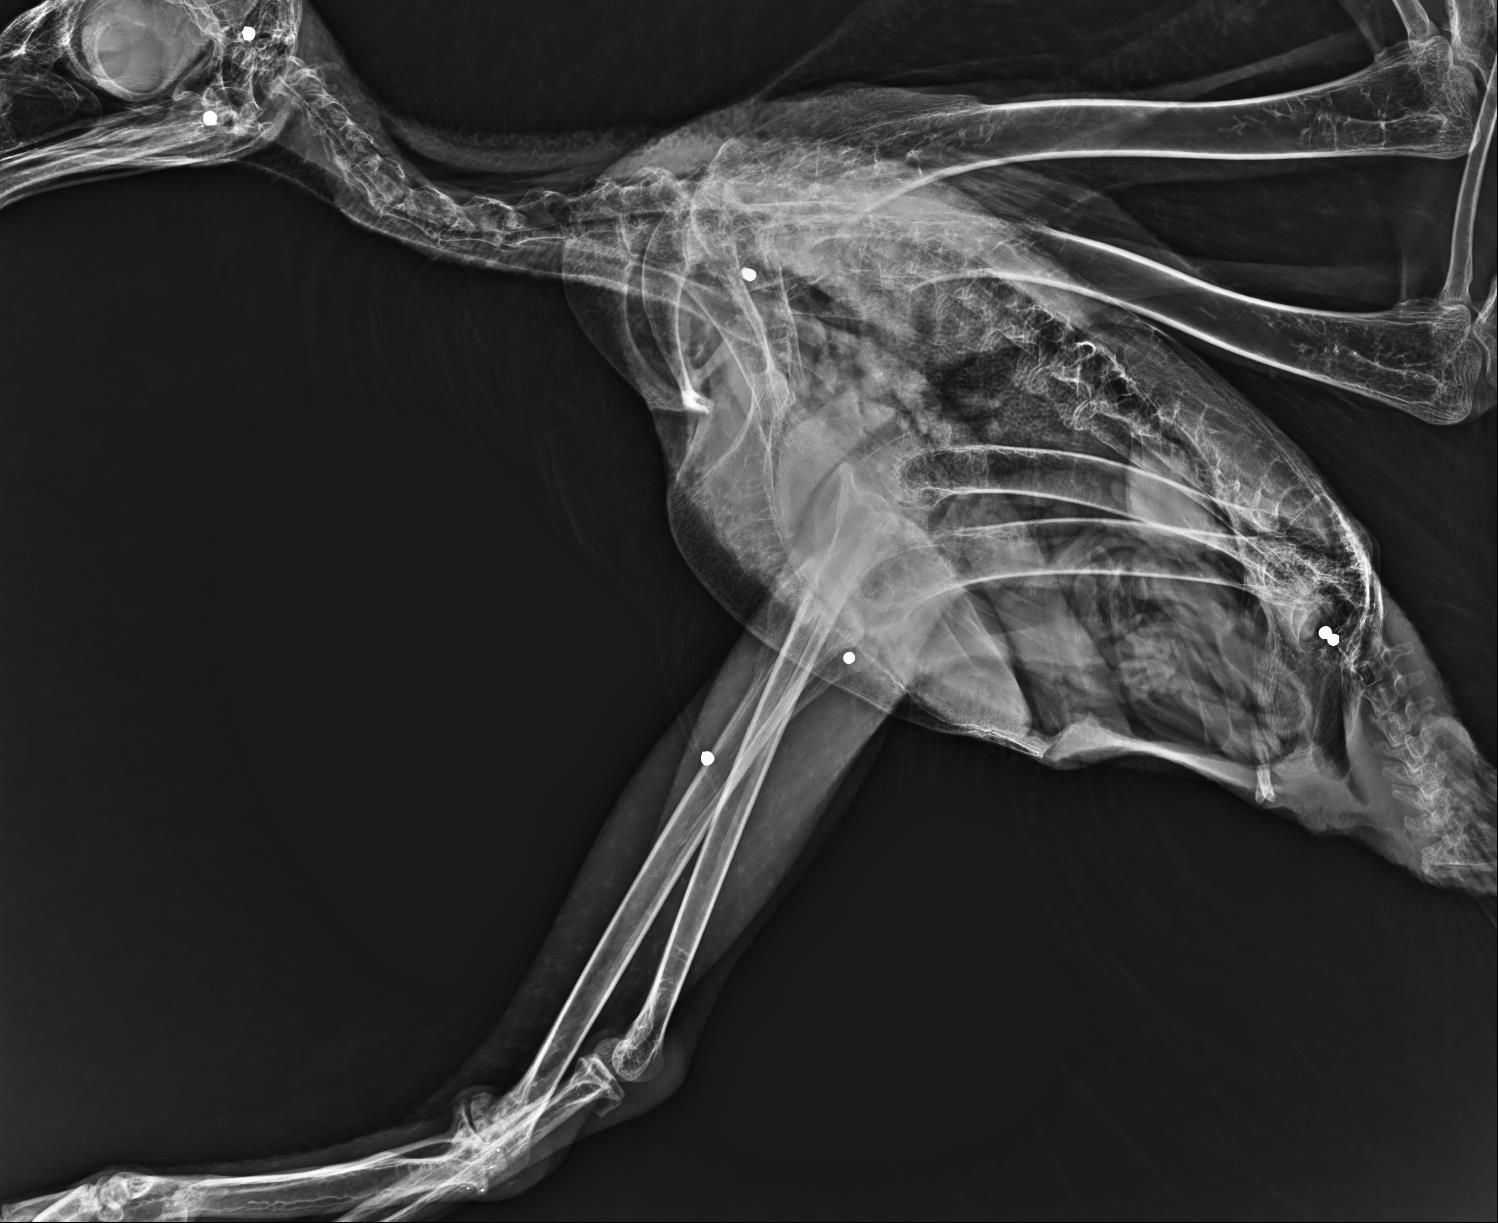

This Wedge-tailed eagle was also shot with an air rifle or pellet gun, over and over again. The radiographs below show the numerous pellets in the head and the body. Thankfully none of the shotgun pellets had entered her digestive tract, which meant lead toxicosis was not an issue. after recovering from her injuries, she was release into the Peter Spitzer free flight aviary at HGRC to begin pre release fitness activity.